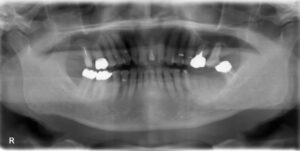

上下臼歯4本欠損症例

BEFORE AFTER 58歳女性/上下4本欠損/インプラント埋込手術 【治療内容】 歯肉の腫れ、痛みでご来院された患…